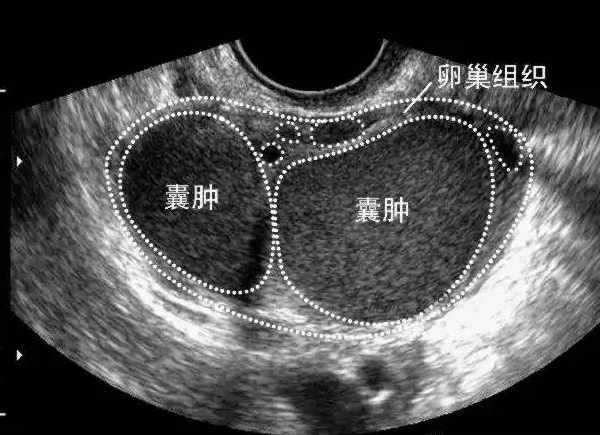

巧克力囊腫會影響試管嬰兒的成功率,主要是巧克力囊腫生長在卵巢區域性,而卵巢是重要的排卵器官。如果在試管嬰兒過程中,促排卵治療的情況下,卵泡壁會出現增厚的現象,因此會影響排卵。如果是要做試管嬰兒的情況下,最好是先把巧克力囊腫做手術治療之後,再考慮做試管嬰兒。巧克力囊腫實際上就是子宮內膜異位症的一種,當檢查到有子宮內膜異位症時,那麼就需要及時的進行治療,否則對身體會造成危害,並且想懷孕的話也就困難。至於巧克力囊腫做試管是否會有影響,又能否促排卵,在文中就能知曉詳情。

巧克力囊腫是不可以促進排卵的,這種情況一般情況下是需要治療的,一般來說,醫生建議在排卵前治療囊腫,以避免影響正常卵子和精子的質量。此外,巧克力囊腫對卵巢也有很大的破壞作用。如果症狀嚴重,將進行手術。因此,早期發現有利於疾病的治療。當治療到差不多的時候,醫生就會給予促排卵的用藥,當促排卵成功後,就可以取出卵子用於受精卵的培育了。

對於有巧囊的人,那麼是可以做試管嬰兒助孕的。克力囊腫多是由子宮內膜異位引起的,任何子宮內膜異位都有可能影響生育,當然也會影響到試管嬰兒的成功率,但一般來講,做試管之前都需要先治療。但如果病情輕微沒有影響輸卵管和卵巢,那麼做試管的影響就不大,如果嚴重的話會令腹腔產生黏連,造成輸卵管堵塞而導致女性不孕。

準備做試管嬰兒的巧克力囊腫患者,手術治療可以提高試管嬰兒的成功率,如果不做手術治療,在移植前3個月接受促性腺激素釋放激素激動劑的治療,也可以顯著提高臨床妊娠率。即便在控制性超促排卵過程中巧克力囊腫仍舊存在,對取卵的影響並不大。因此,巧克力囊腫患者做試管嬰兒並不是很難成功。